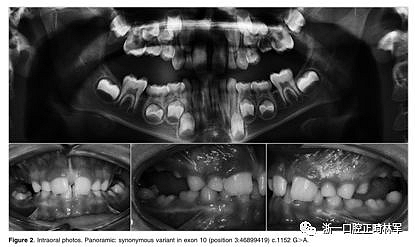

最后,在數(shù)據(jù)庫(kù)中以前沒有報(bào)道的錯(cuò)義變體在外顯子16 c.1765 T>C p.Trp89Arg中發(fā)現(xiàn)。 在同一家庭的三個(gè)成員 - 母親,女兒和兒子(圖3A,B)中發(fā)現(xiàn)的錯(cuò)義變體-負(fù)責(zé)用精氨酸p:Trp89Arg取代氨基酸色氨酸,這是一種具有不同化學(xué)特性的氨基酸。該突變發(fā)生在PTH1R蛋白質(zhì)的胞質(zhì)結(jié)構(gòu)域中,并參與受體與激活細(xì)胞內(nèi)級(jí)聯(lián)信號(hào)的G蛋白的相互作用。此外,計(jì)算機(jī)結(jié)果表明,PTH1R蛋白質(zhì)中的這種氨基酸取代改變了蛋白質(zhì)的結(jié)構(gòu)和功能,因?yàn)樗l(fā)生在蛋白質(zhì)的催化結(jié)構(gòu)域內(nèi)。

正畸文獻(xiàn)閱讀--原發(fā)性萌出失敗:混合牙列的臨床和遺傳學(xué)研究

正畸文獻(xiàn)閱讀--原發(fā)性萌出失?。夯旌涎懒械呐R床和遺傳學(xué)研究

圖3.(A,B)兩兄弟的口內(nèi)照片。全景:外顯子16中的家族錯(cuò)義變體c.1765 T>C p.589 W>R

屬于2號(hào)家庭的小女兒(2:2)表現(xiàn)出更復(fù)雜的臨床表現(xiàn),缺乏永久性以及暫時(shí)性系列和囊性結(jié)構(gòu)元素的萌出(圖3A,B)。在哥哥(II:1;圖3A,B)中發(fā)現(xiàn)由于包括多顆恒牙的嚴(yán)重的雙側(cè)后牙開合。最后,患者II:1和II:2的母親表現(xiàn)出雙側(cè)上頜第一磨牙和下磨牙的包埋。發(fā)現(xiàn)前磨牙層面沒有咬合接觸(圖3A,B)。

本研究中確定的低咬合的臨床特征與PFE基于基因診斷和萌出障礙診斷標(biāo)準(zhǔn)的應(yīng)用相一致。對(duì)特定相關(guān)牙科特征的仔細(xì)臨床檢查包括以下內(nèi)容:至少一顆牙包括低咬合,局限于后部區(qū)域,單側(cè)(38%;圖1A)和雙側(cè)呈現(xiàn)(35%;圖1B和2),至少有一個(gè)暫時(shí)性后牙(48%暫時(shí);圖1A,B和3A; 55%永久性,圖3B)。此外,觀察到牙面特征如下:由于受影響側(cè)的側(cè)向開放咬傷的嚴(yán)重程度而引起的垂直骨骼不對(duì)稱(35%;圖1A,B和圖3A,B);由下頜骨側(cè)向偏離組成的面部不對(duì)稱(圖1A,B和圖2;表4)。這種不對(duì)稱在單側(cè)開合患者中更為明顯。進(jìn)一步發(fā)現(xiàn)受影響的患者與先前報(bào)道的患者存在上頜骨收縮和III類牙齒/骨骼關(guān)系(28%;圖1A,B和圖2)。至少有一例患者出現(xiàn)了相對(duì)于9名患者的低咬合。表4總結(jié)了PTH1R的表型結(jié)果和相關(guān)的突變分析(N = 8)。